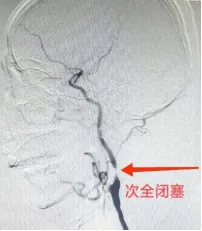

术前颈动脉造影